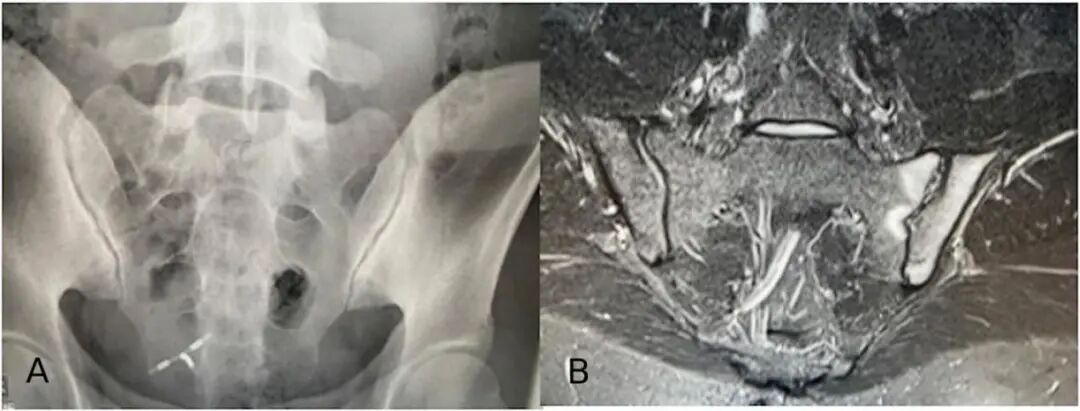

SIJ平片通常是识别SIJ受累的首选影像学方法,但该方法存在重大的局限性:在症状出现后数年,骨盆平片扫描才能发现SIJ损伤。此外,即使在有经验的读片者中,SIJ的平片判读也通常具有挑战性。如果根据临床特征和常规X线平片无法做出诊断,建议进行SIJ的MRI扫描(如图4)。

图4 非影像学中轴型脊柱关节炎的影像学表现

SIJ MRI扫描若能看到符合ASAS定义的BME,则增加了axSpA诊断的可能性,尤其是同时存在结构改变时。然而,临床医生应该记住,BME对axSpA的特异性低于先前认知,BME也可发生在非特异性背痛、致密性骨炎、健康人、产后女性、娱乐性跑步者和运动员患者中(深处/广泛的病变仅见于axSpA患者)。